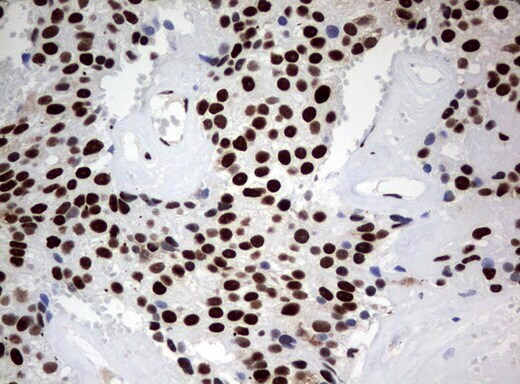

- Immunohistochemical staining of paraffin-embedded human lymph node tissue using anti-ZSCAN18 mouse monoclonal antibody. (UM500081; heat-induced epitope retrieval by 10mM citric buffer, pH6.0, 120°C for 3min)